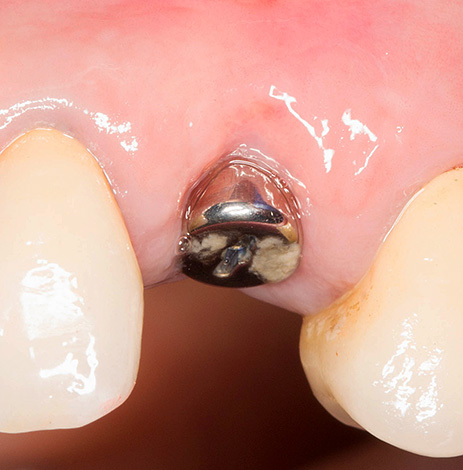

Consequentemente, após realizar uma incisão circular com um mucótomo e remover o círculo gengival excisado, segue-se um estágio completamente padrão de preparação do orifício para a colocação do implante - expansão e aprofundamento dos cortadores.

- Em seguida, segue a instalação do implante e controla a profundidade de sua introdução;

- Depois disso, o gingiva anterior é instalado;

- Em conclusão, o paciente cumpre as recomendações prescritas pelo médico (antibioticoterapia, regime de economia, etc.).